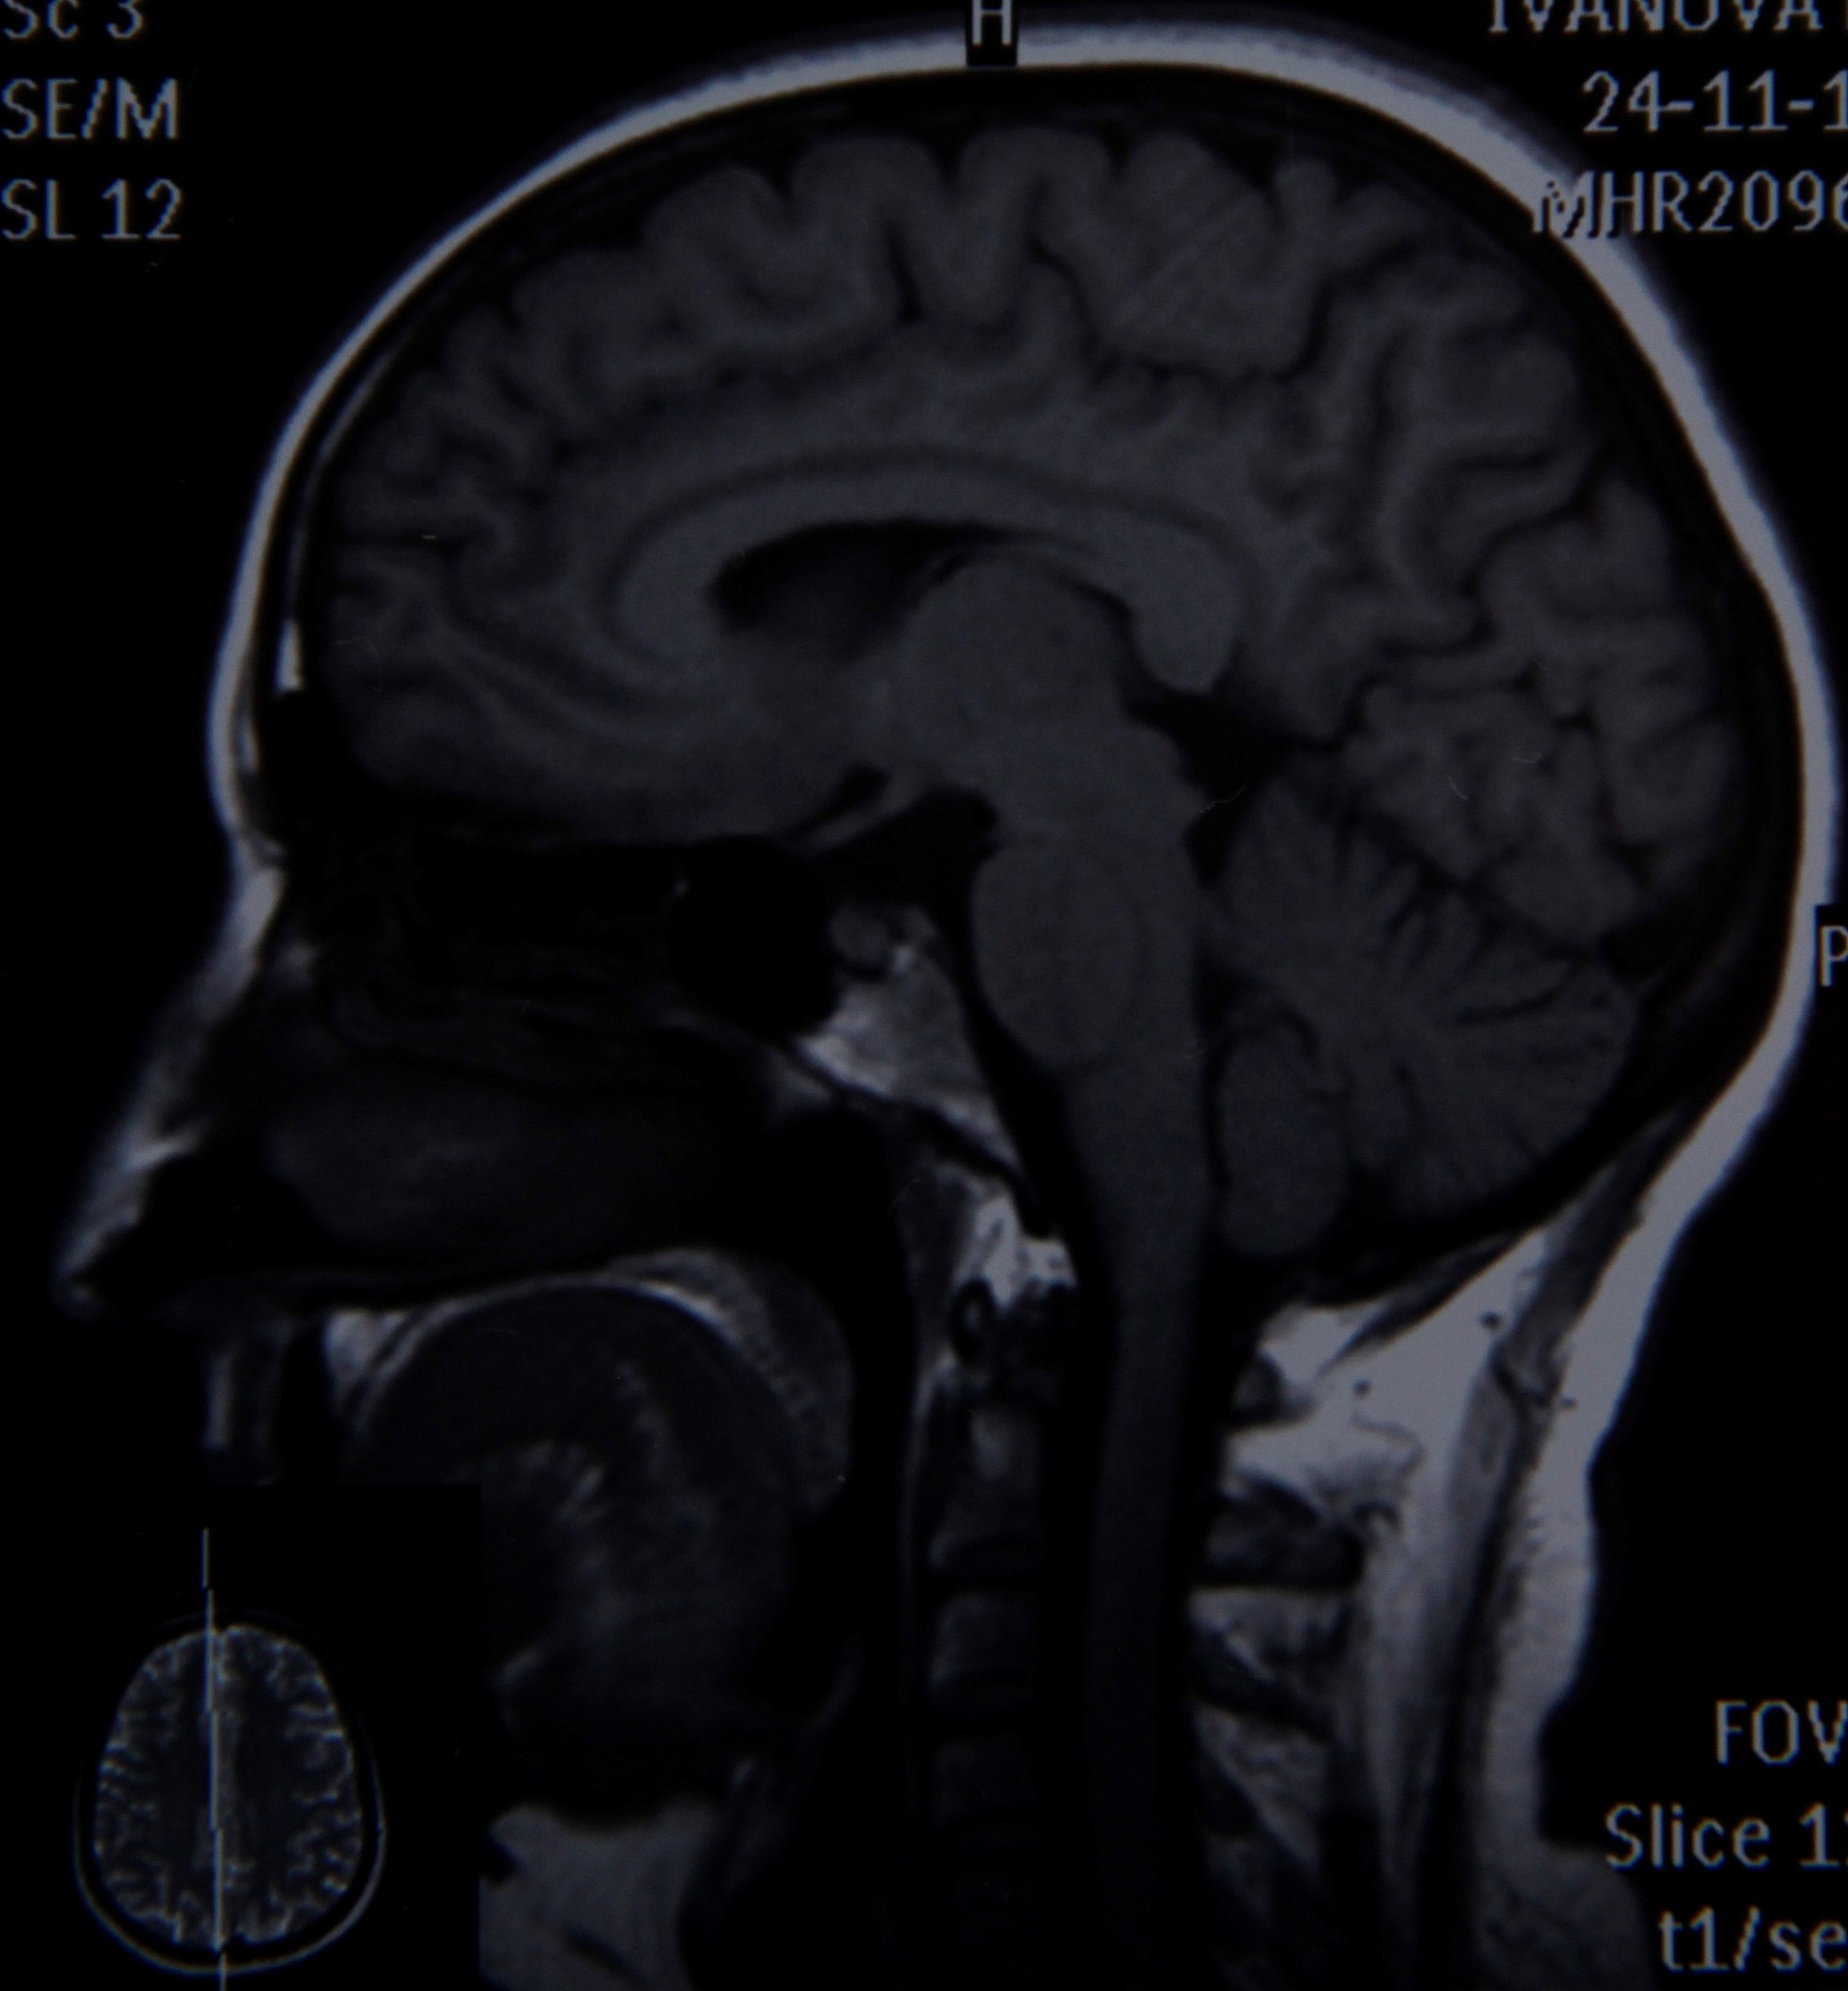

脑膜刺激征三大主征为颈强直、克尼格征阳性、布鲁津斯基征阳性,提示脑膜炎症或出血。